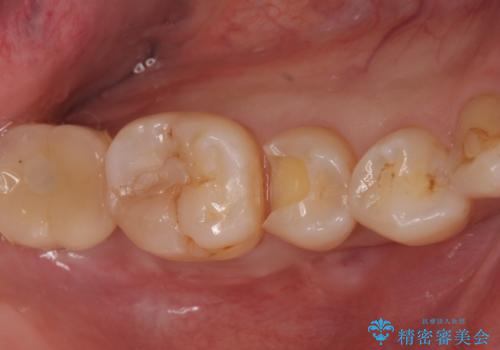

- フロスをすると引っかかる、食べ物がよく詰まるとのことで来院。

精査したところ詰め物が欠けており、物が挟まりやすく不潔になっていました。

また、小さめですが、虫歯になっていました。

そのままだといくら歯磨きを頑張っても虫歯が進行してしまいやすい状態となっていたため治療を勧めました。

虫歯を除去し、白くて目立たないセラミックインレーによる修復を行いました。

セラミックインレーの装着によりフロスが引っかからなくなりました。また、食べ物も詰まらなくなり、とても満足していただきました。